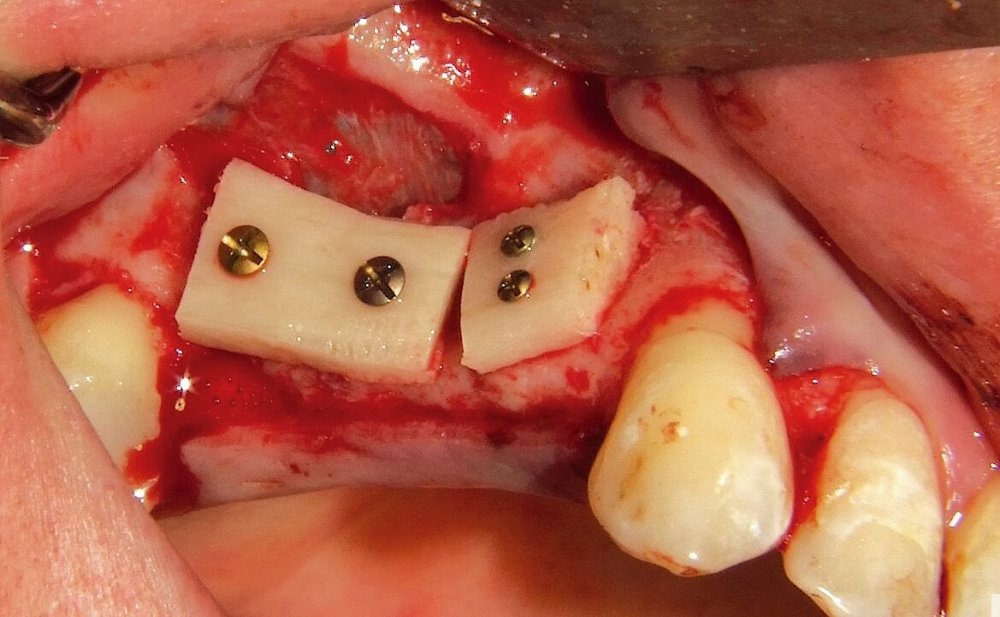

Bərpa texnikasının müəyyən edilməsi, sümüyün hansı bölgədə, hansı miqdarda itirilmiş olmasına bağlı olaraq müəyyənləşdirilir. Bərpa üçün tətbiq edilən sümük materialları pasiyentin öz donor bölgələrindən xüsusi metodlarla qazanılmış sümüklər, o cümlədən digər fərdlərdən alınmış və xüsusi qaydada hazırlanmış materiallar, heyvan mənşəli sümükəvəzləyici materiallar və sintetik materiallar olaraq ayrılır.

Bərpa zamanı yerinə görə bu materiallar ya ayrı-ayrılıqda, ya da kombinə olunmuş şəkildə tətbiq oluna bilir. Gündəlik təcrübədə həmçinin pasiyentdən götürülmüş qan nümunələrindən alınmış yüksək bərpaedici xassəyə malik materiallar (PRF) da uğurla tətbiq olunur. Sümükartırma metodlarının tətbiqi sayəsində, çənədə implantların yerləşdirilməsi üçün yetərsiz sümük həcmi olan bölgələrdə sümük miqdarı yetərli duruma gətirilir, uyğun boy və diametrə uyğun implantlar uğurla tətbiq olunur.